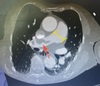

4

5